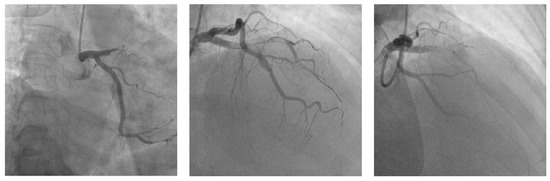

T and Small Protrusion (TAP) Technique in Bifurcations: Coronary Artery Disease in Acute Myocardial Infarction Patients after COVID-19 Pneumonia

Ischemic coronary artery disease in all its forms remains the main cause of death worldwide. Coronary artery bifurcation lesions are a challenge because of their complexity and possible complications. The goal of treating bifurcation lesions is the optimal revascularization of the main vessel without compromising the side branch. Although the study of bifurcation stenting aims to keep the side branch viable, the outcomes regarding major acute cardiovascular events and survivability are related to the optimal treatment of the main vessel. There are many trials that have tried to evaluate the best technique to use with respect to bifurcation lesions, and early studies support provisional stenting as the election treatment. More recent trials highlighted the superior outcomes of the double kissing crush technique used on unprotected distal left main bifurcation lesions. In patients with acute myocardial infarction, two-stent techniques were avoided because of the prolonged procedural time in unstable patients, with high risks of complications. We present the case of a 53-year-old woman with multiple cardiovascular risk factors (dyslipidemia, hypertension, active cancer, post-COVID-19 state) and acute antero-lateral myocardial infarction who underwent primary coronary intervention with the use of the TAP technique for stenting the bifurcation culprit coronary lesion (left anterior descendent artery and first diagonal artery). Full article

Show Figures

Graphical abstract